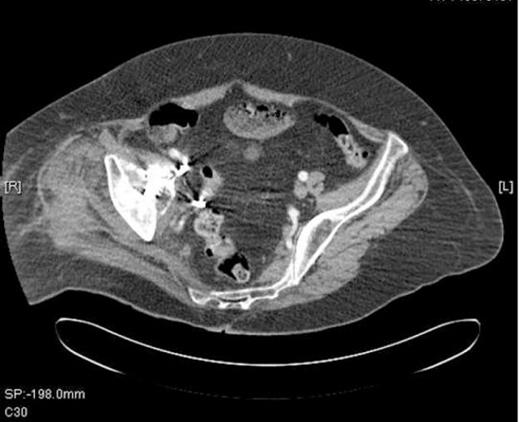

To avoid thrombus escaping from the iliac vein at the time of revision, a vena cava filter was inserted from the contralateral femoral vein (Figure 3).

Inferior vena cava (IVC) filter inserted prior to revision surgery